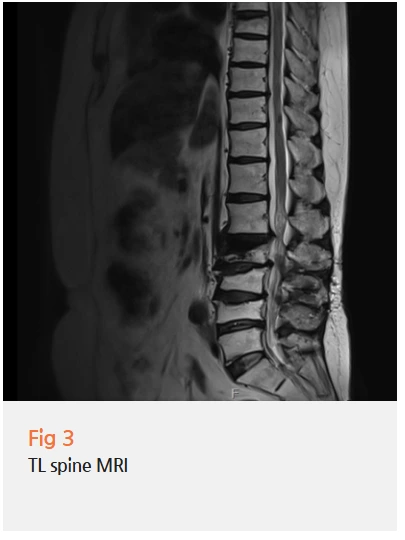

환자분은 허리 통증과 다리 저림도 여전히 있으셨거든요.

허리 수술을 이미 받으셨는데도

증상이 계속되는 상황이었기 때문에,

척추 문제도 함께 봐야 했습니다.

김환희 원장님과 협진을 통해 환자분의 허리 상태를 다시 확인했고,

요추협착증과 허리 골절이 남아있다는 걸 알게 됐습니다.